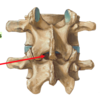

two main segments of the typical vertebrae

arch and body

orientation of facets: cervical

oblique/ horizontal plane

orientation of facets: thoracic

coronal plane

orientation of facets: lumbar

sagittal plane